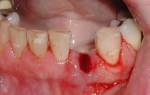

Крайне неприятным последствием пародонтоза является кровоточивость десен. Увеличение межзубных щелей и возникновение подвижности зубов. Оседание десен чревато оголением шеек и корней зубов и возникновению эффекта клиновидных зубов. Болезнь не только сопровождается болезненными ощущениями зубной эмали на термические и химические раздражители, но и существенно снижает самооценку больного. Болевые ощущения мешают полноценному питанию и общению, по утрам усиливается неприятный запах из ротовой полости.